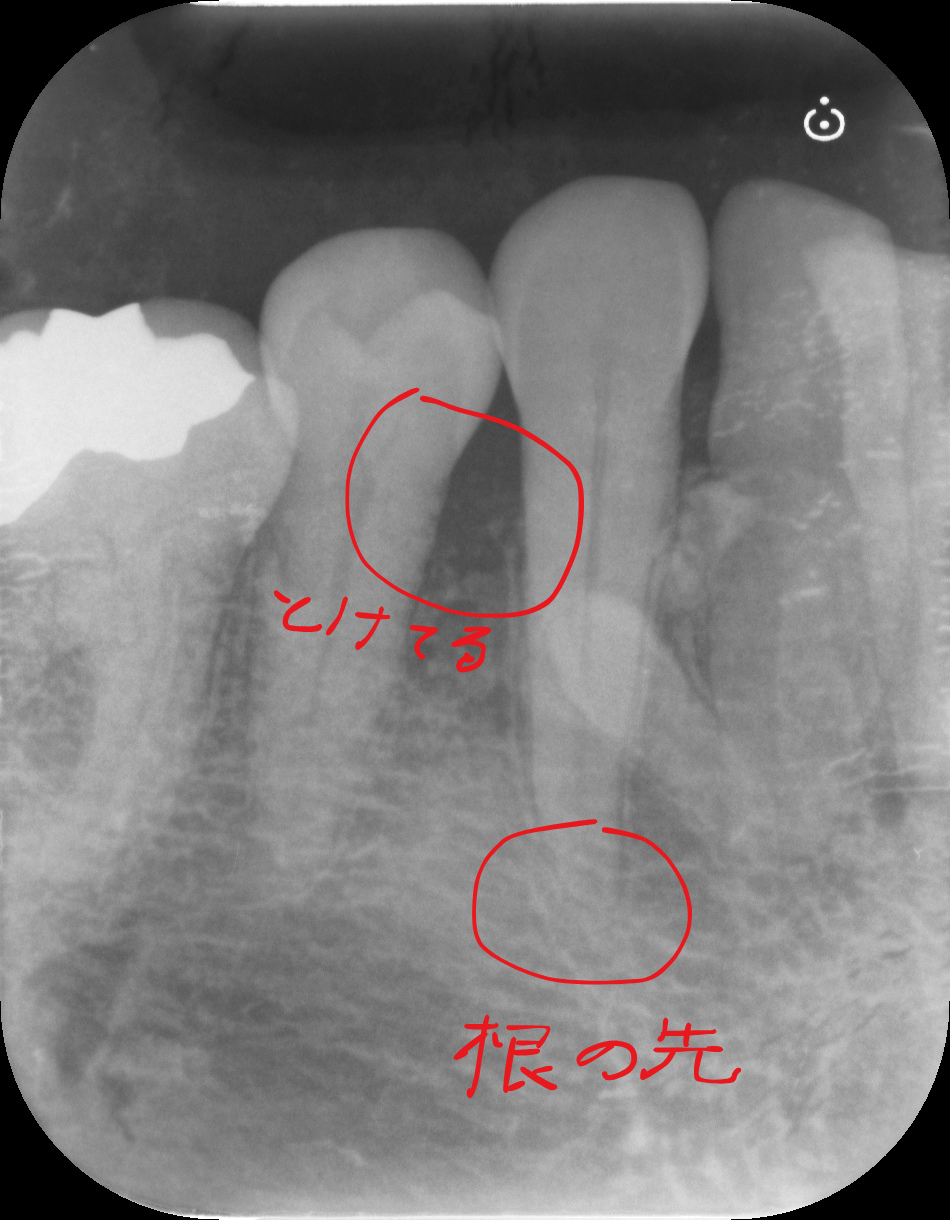

こんなときはレントゲンを撮るのが大切ですね。

レントゲンでは歯周病の所見も認めますが、レントゲンのみでは15mmもプローブが入るような写り方はしていません。

おそらく何か他にも原因があるのでしょう。(歯科関係者のみなさん過剰歯があるのは無視してください)

上のレントゲンからは少し骨が溶けている様子が見られます。